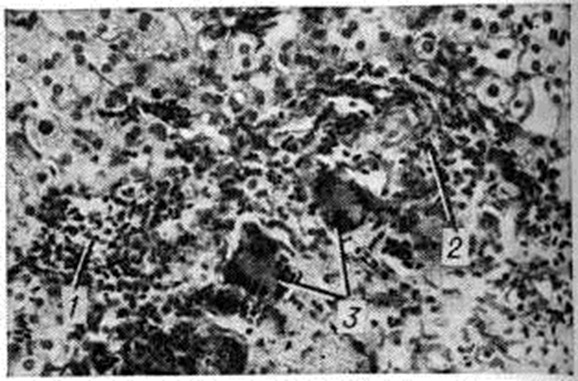

Хронический очаговые Гепатит (например., при бруцеллёзе, саркоидозе, туберкулёзе, альвеококкозе) имеют специфическую патологический картину, свойственную общей патоморфологии этих заболеваний (рисунок 1—4).

При поражении печени некоторыми грибками (актиномикоз), простейшими (амебиаз, балантидиаз) и гельминтами (аскаридоз, клонорхоз, фасциолез) наблюдаются гнойные Гепатит с множественными абсцессами. И. В. Давыдовский подчёркивал, что гранулематозный процесс более стереотипен, чем специфичен, так как обусловлен иммуногенезом и однообразием образующих гранулему клеточных элементов, которые при различных нозологических формах отличаются лишь своими сочетаниями.